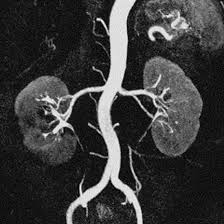

MR Angiography of the Renal Arteries with Contrast

MRI Angiography or MRA is therefore a more refined imaging that uses the MRI to establish blood flow patterns in the human body. Of all the endovascular imaging techniques, this is regarded as non-invasive and greatly useful when assessing the blood vessels devoid of the dangers of using ionising radiation such as in X-ray and CT scans. MRA uses strong magnets and radio waves in order to create clear pictures of vessels. An IV contrast agent, usually, gadolinium, is administered to help make the blood vessels stand out. Most suitable for visualising arterial structure with regard to blood flow. Measures the velocity of blood flow, offers complementary functional details concerning the arterial cardiovascular. The imaging modality of MRA is applied to identify stenosis, aneurysms, and vascular malformation. It helps the surgeons to visualise the arteries prior operations. It also helped in the assessment of the blood supply to tumours, for decisions on the kind of treatment to be given. However, there are contraindications to MRA, and patients with particular types of implants or patients with severe renal impairment should not undergo this modality.